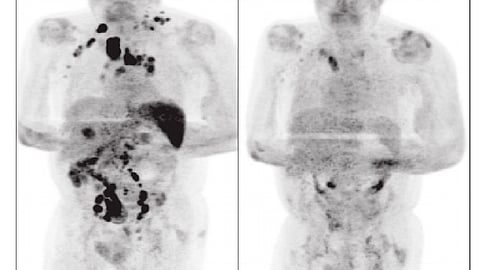

El misterioso caso fue presentado por los doctores Sarah Challenor y David Tucker en la revista British Journal of Haemathology, quienes explicaron que el hombre de 61 años fue diagnosticado con cáncer por linfoma de Hodgkin en etapa 3, lo que quiere decir que la enfermedad ya estaba por todo su cuerpo.

Luego de que fue dado de alta, el hombre no volvió a la clínica hasta cuatro meses después a una consulta de rutina, y ese día fue cuando los doctores descubrieron que el paciente mostró una notable mejoría ya que los ganglios ya no estaban inflamados.

Los especialistas consideraron que la infección por SARS-CoV-2 desencadenó una respuesta inmunitaria antitumoral como se describió con otras infecciones en el contexto de linfoma de Hodgkin de alto grado.